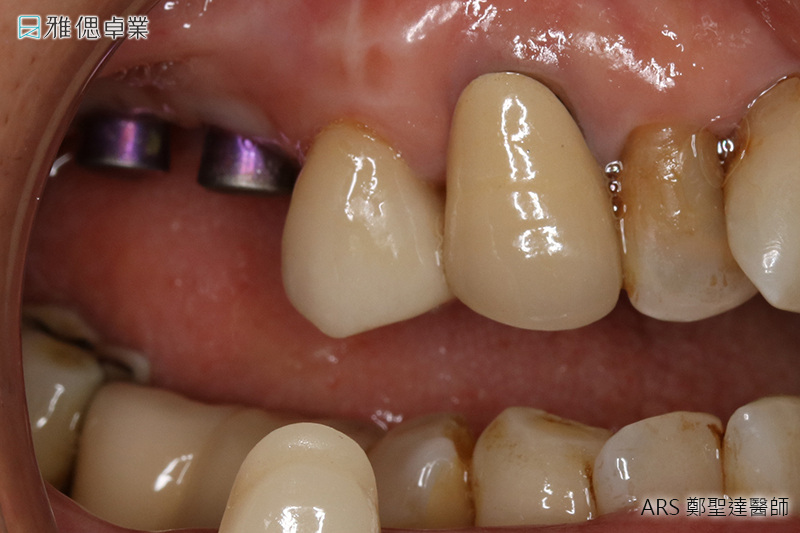

STEP2 植入人工植牙手術

局部麻醉後,醫師會利用手術導引板抓取精準位置與角度,將植體放入齒槽骨中,先進的數位導引板不僅能縮小手術誤差,同時也可控制傷口範圍,使植牙術後的癒合更為迅速。植入人工牙根後,骨細胞就開始進行植體的整合。

STEP3 牙齦塑形

植體在人體內3個月後,骨整合已經足夠支持咬合力,為了塑造未來牙套的牙齦型態,醫師會在植體上端接入牙齦成形帽,使牙齦生長為理想形狀。